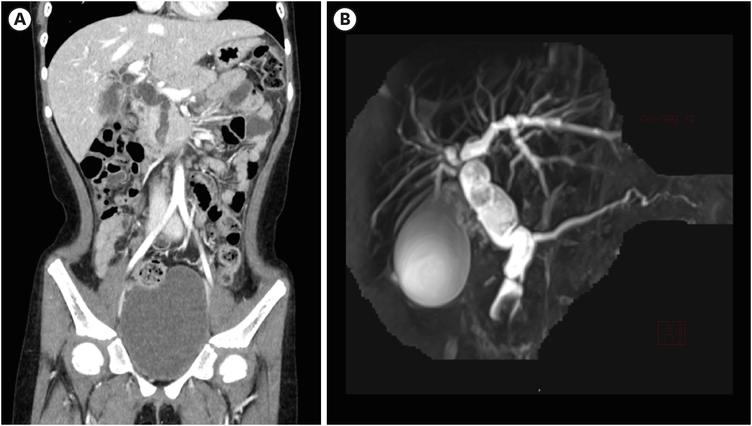

A 7-year-old girl visited the pediatric department of Asan Medical Center for endoscopic retrograde cholangiopancreatography (ERCP) to remove a distal common bile duct (CBD) stone. She was previously healthy and visited a nearby hospital due to abdominal pain and vomiting lasting for 13 days, and jaundice progressed the day before hospital visit. Computed tomography (CT) revealed tortuous dilatation of the extrahepatic bile duct abruptly narrowed in the distal CBD level with several distal CBD stones and anomalous pancreaticobiliary ductal union (APBDU, P-C type). The common channel was measured as 1.9 cm in length. These findings suggested type I CC related to APBDU. Secondary cholecystitis, cholangitis, and pancreatitis were additionally found (Fig. 1A). The same findings were confirmed on magnetic resonance imaging (Fig. 1B). After failure of the first ERCP at the previous hospital, she kept non per oral for one week, but symptoms and lab findings were never relieved (Table 1). So, she was determined to transfer to Asan Medical Center. ERCP was performed. Both pancreatic and CBD were successfully cannulated, and a 10 Fr. Endoscopic retrograde biliary drainage stent was retained in the bile duct for remnant stone excretion. No residual stone was found in follow-up CT in 3 days post ERCP (Fig. 2). Serum levels of liver enzymes, bilirubin, and amylase/lipase decreased to the normal range. Two months later, robotic CC excision and Roux-en-Y hepaticojejunostomy were performed. Severe adhesion and fibrosis around the CC reflecting chronic inflammation were noted. Type I CC was identified, and CBD was resected proximally above the cystic duct and distally at the upper border of the pancreas head. The patient recovered without acute complications. In ultrasonography of post-operative day (POD) 7, no abnormal finding was observed except a small fluid collection around hepaticojejunostomy. She was discharged on POD 9. In the permanent biopsy, edematous mucosal change of gallbladder (GB) and cystic duct was observed, but the diameter of the cystic duct was within the normal range (0.4 cm). In microscopic findings, papillary hyperplasia was identified. The resected CC was 2 cm in length and 2 cm in the widest circumference. It was pathologically confirmed as a CC, accompanying fibrosis and wall thickening changes of CBD, and low-grade BilIN was identified from the resected CC (Figs. 3 and 4). Papillary hyperplasia in GB suggests chronic inflammation in the biliary system due to CC such as BilIN. There was no involvement in the cystic duct and GB as in Type VI.

Fig. 2

Computed tomography follow-up after endoscopic retrograde biliary drainage insertion. (A) 3 days and (B) 7 days post procedure. Improved bile duct dilatation was observed.